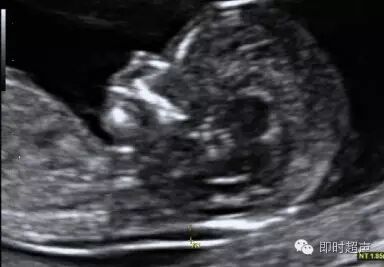

胎儿NT检查时的正中矢状切面图,如下:

即正侧位

看这张B超图,图中的胎儿侧脸面对“镜头”,鼻子和脸向上,NT在画面的下方。这样的画面就是正矢位(看到侧脸)。图中的胎儿是头右,当然头朝左也是正确的。